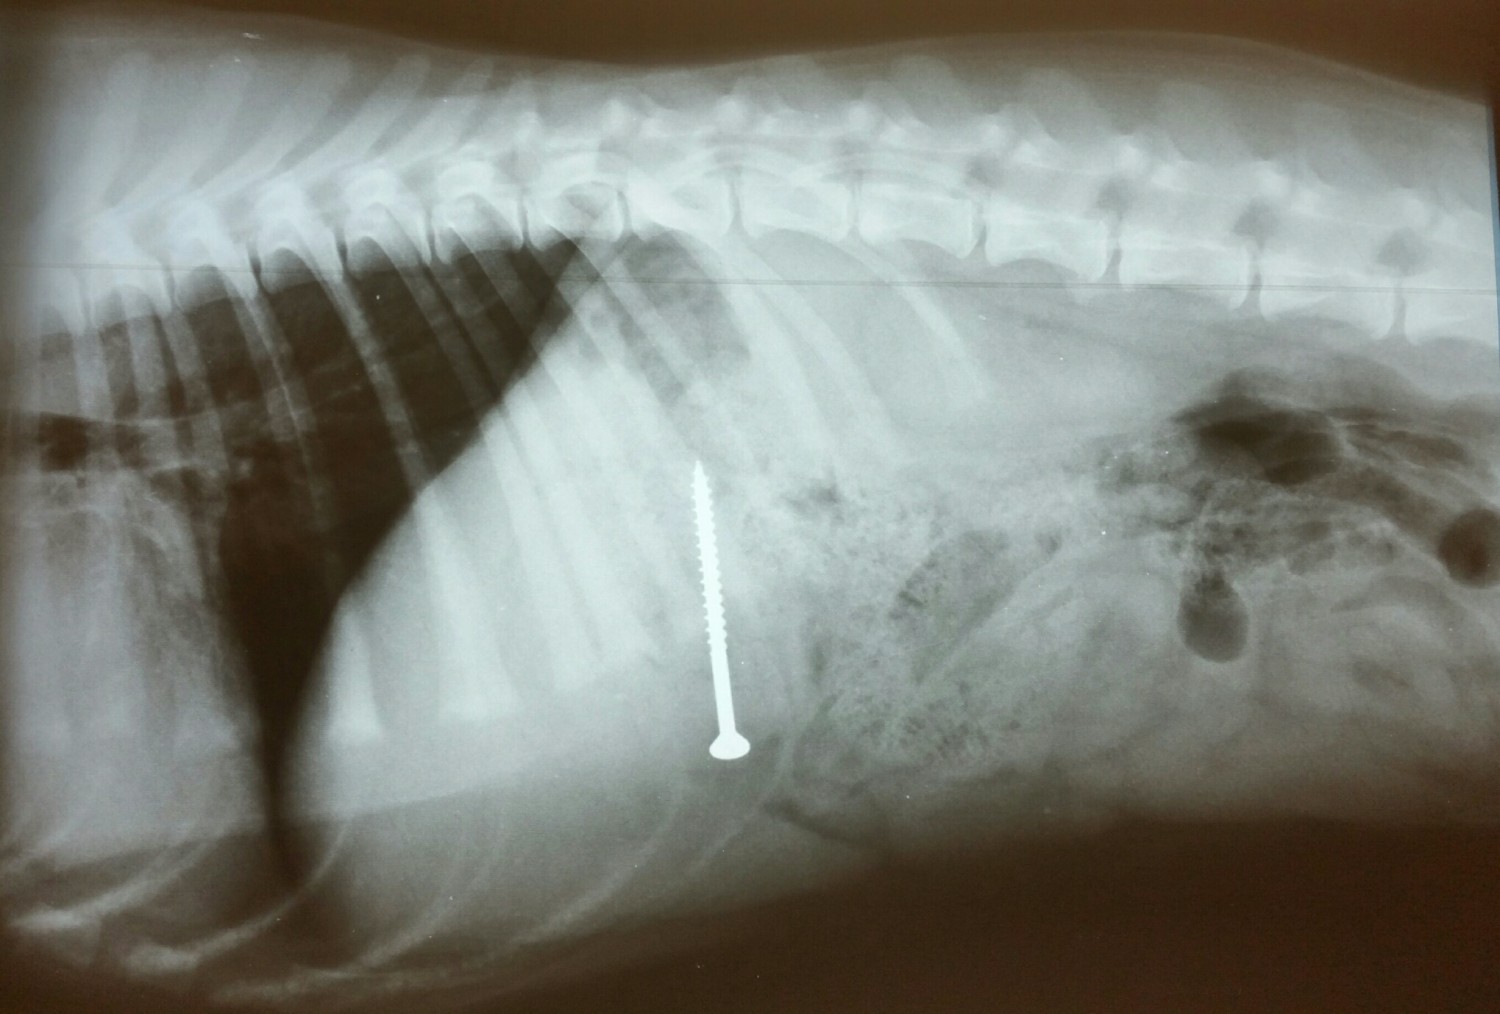

Foreign Body Dog Stomach Xray. Abdominal sonography is a sensitive method for detecting intestinal plication and the linear foreign body will often be seen as a discrete line within the lumen of the intestine. Gesundes Tierfutter aus eigener Herstellung - entwickelt produziert in Deutschland. This is the first report of a metallic foreign body in the spleen of a dog. In most cases a veterinarian will assess the dogs condition with X-rays or other imaging scans to determine the safest and most effective approach.

Veterinary Medical and Surgical Group San Juan. Young cats and young large-breed dogs are more likely to present with signs of foreign body obstruction than older animals. Often the foreign body cannot be seen on the x-ray but the consequences of the foreign body obstruction are visible. Clinical signs are variable depending on duration degree and location of the foreign body but often include vomiting and anorexia. Gastrointestinal foreign bodies are an important differential diagnosis for patients presented for vomiting and radiography remains the main initial imaging modality in these cases.

Gossypiboma is the term sometimes used to describe the foreign body reaction to a surgical sponge left within the body for a long period Fig 45. The dog recovered uneventfully. Laguna Grove Veterinary Hospital Laguna Niguel Calif. The animal had abdominal discomfort with a tucked-up abdomen and occasional vomition. If a foreign body becomes stuck at any point in the digestive tract from the mouth to the esophagus stomach or intestines so that it partially or completely blocks the flow of nutrients and impairs blood flow to the bowel then the foreign body becomes a life-threatening obstruction.

In most cases a veterinarian will assess the dogs condition with X-rays or other imaging scans to determine the safest and most effective approach. Gastric foreign body is a term that refers to any material other than food that is eaten and that results in a serious digestive problem in the stomach. If a foreign body becomes stuck at any point in the digestive tract from the mouth to the esophagus stomach or intestines so that it partially or completely blocks the flow of nutrients and impairs blood flow to the bowel then the foreign body becomes a life-threatening obstruction. The string may cut through the frenulum of the tongue and bury. Often the foreign body cannot be seen on the x-ray but the consequences of the foreign body obstruction are visible.

Diarrhea weight loss lethargy and signs of septic. They will pump air into his stomach or make use of Barium to locate any blockage. In addition your veterinarian may recommend blood and urine tests to assess whether the patients health has been compromised by the obstruction or to rule-out other. Radiographs revealed a foreign body in a distended stomach. The procedure used for foreign body removal in dogs will depend on the nature and location of the obstruction.